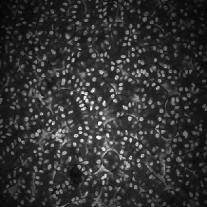

Figure 3 shows the synthetic images generated by our proposed method. The left column indicates original images whereas middle column shows synthetic images artificially generated from corresponding synthetic binary images provided in right column. As can be seen from Figure 3, the synthetic images reflect characteristics of the original microscopy images such as background noise, nuclei shape, orientation and intensity.

Additionally, two synthetic data generation methods between CycleGAN and SpCycleGAN from the same synthetic binary image are compared in Figure 4. Here, the synthetic binary image is overlaid on the synthetic microscopy image and labeled in red. It is observed that our spatial constraint loss reduces the location shift of nuclei between a synthetic microscopy image and its synthetic binary image. Our realistic synthetic microscopy volumes from SpCycleGAN can be used to train our modified 3D U-Net.